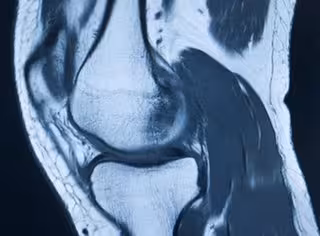

Imagen Médica De Articulación De Rodilla.

En concreto, IBV está investigando en el modo de realizar el análisis de las imágenes médicas, que se utilizan para diagnosticar a los pacientes. Para ello, el centro ha desarrollado metodologías de cribado o preclasificación de patologías osteoarticulares, para la detección de lesiones, mediante la utilización de técnicas de inteligencia artificial (AI).